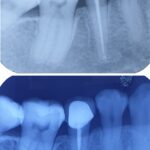

Beduya Dental Center is a TMJ-centered clinic which offer services specialized in TMD and Orofacial Pain, Orthodontics, Implantology, General Dentistry and Cosmetic Dentistry.